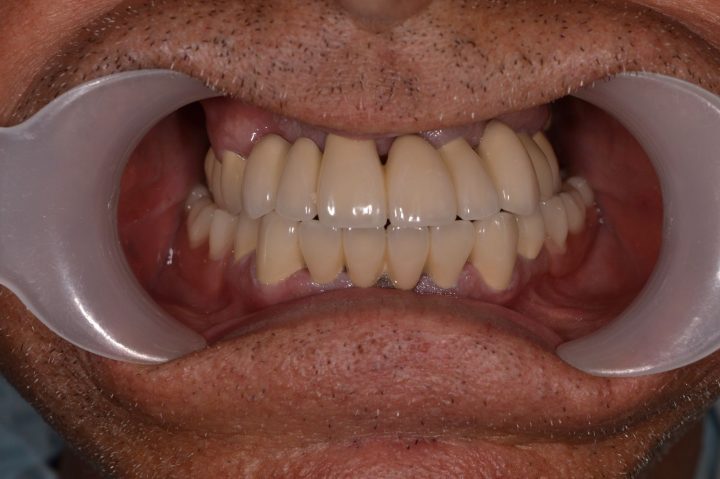

Mark

Mark ist ein englischer Patient bei uns, der sich in seinem ganzen Leben nach weißen Zähnen gesehnt hat. Sein Fall ist unregelmäßig, weil er früher eine andere ungarische Zahnklinik besucht, hat, wo er Implantate bekommen hat. Aber er war mit der Patientbetreuung nicht zufrieden.

Auf den Rat von seinem Freund hat er so entschieden, dass er die Behandlung in der Zahnklinik Centrocc Dental beenden möchte. Er hat diese Entscheidung nicht bereut, und hat die Klinik seinen alten Traum verwirklicht.

Auf seine Implantate haben wir durch Frau Dr. Erdélyi insgesamt 24 Stück Metallkremaik Kronen bearbeitet.